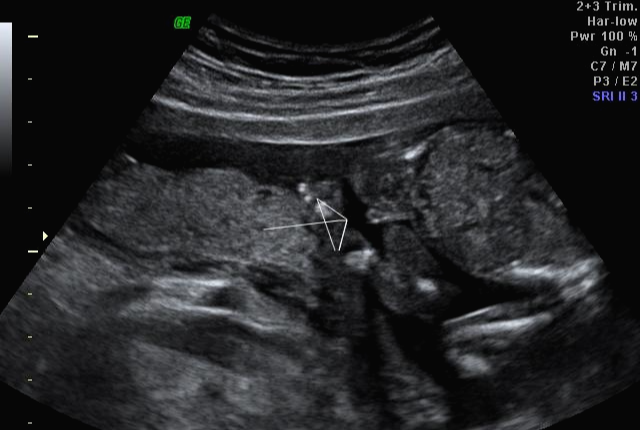

그리고 초음파 봐주시는 분께서 13주차가 되면 정확히 알 수 있으니 다음 주에 오라고 하셔서 일주일 뒤 다시 방문을 했습니다. (위에 사진은 12주 차 때 아들이라고 보여주신 초음파 사진이에요~ 화살표 보면 툭 튀어나와있는 부분을 보여주면서 아들이라고 하셨어요~)

아 진짜 전문가는 다르구나~ 이렇게 이른 주수에도 성별을 알 수가 있구나 생각을 했지만 이 시기 때는 성별을 정확히 알 수 없다는 글들을 봐서 살짝~ 의심스럽기도 했지만 그래도 100프로라니깐 ㅎㅎ 믿어보았어요~ 근데 위에 사진을 보면 성별을 알 수 있는 각도 법이 있는데 각도가 딸 같아서 긴가민가~하긴 했지만 의심은 잠시! 전문가 분을 믿기로 ㅋㅋㅋㅋ